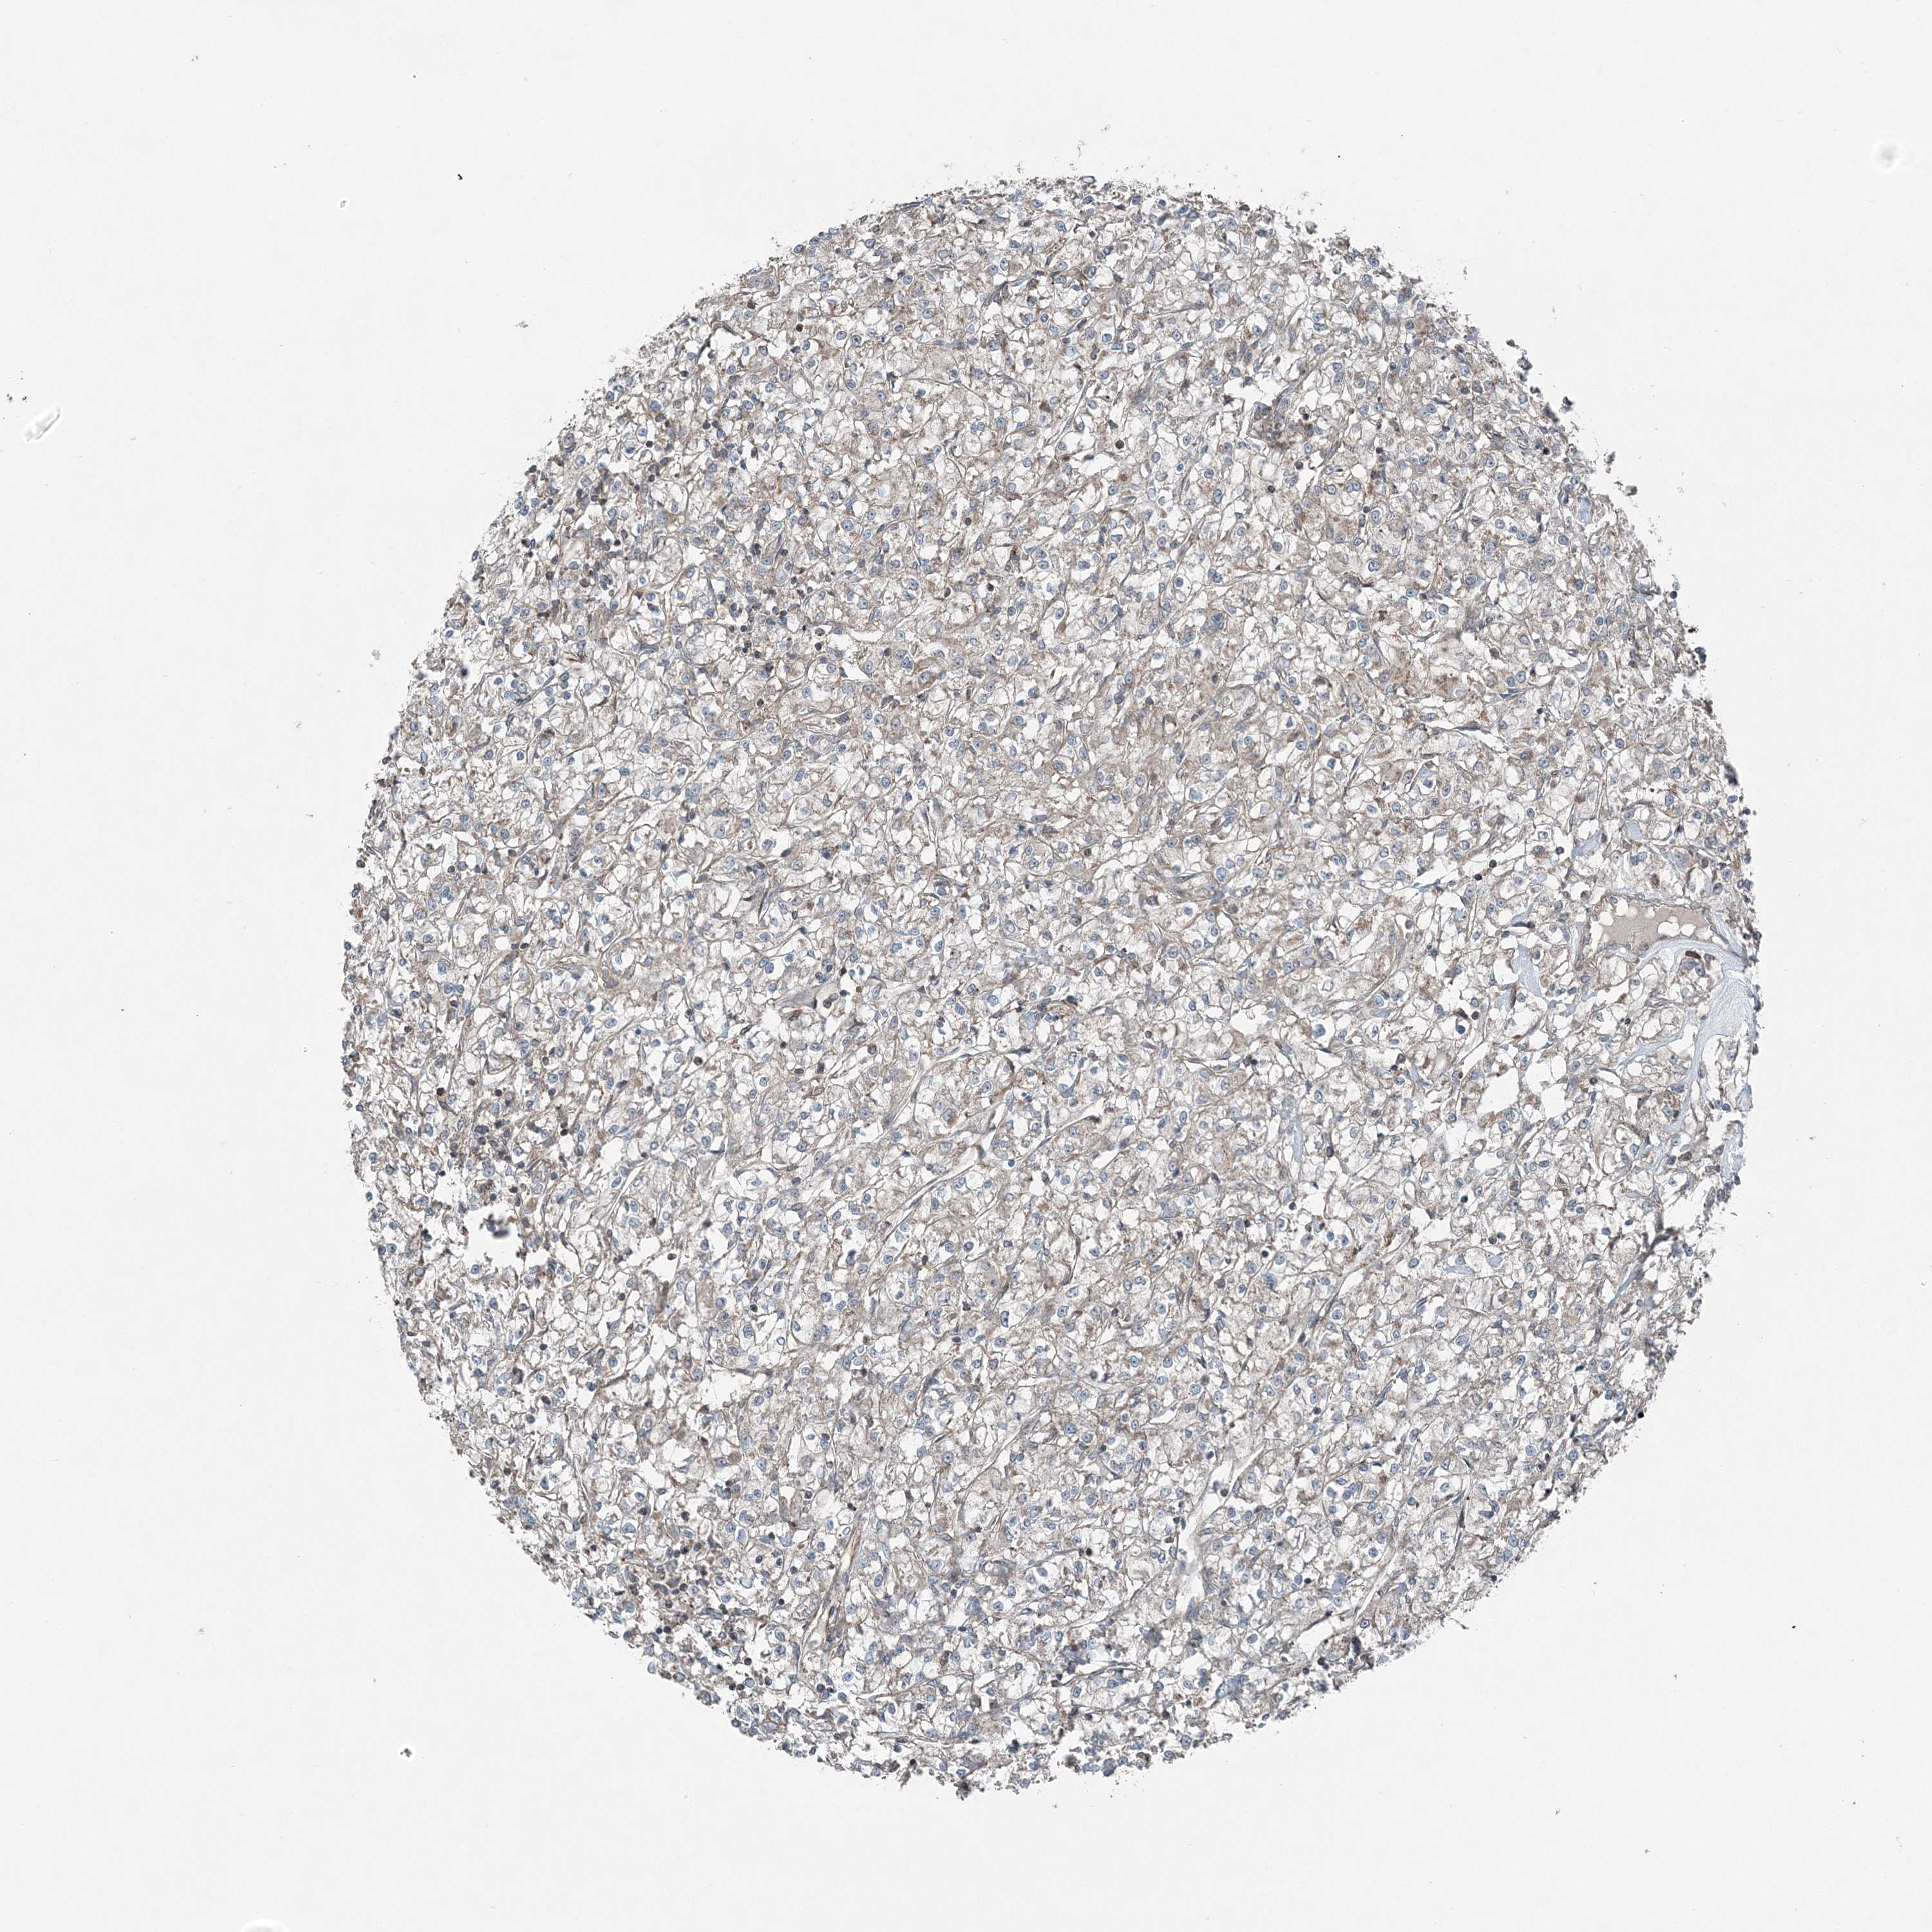

TCGA RNA samplesi

RNA-seq data is reported as average FPKM (number Fragments Per Kilobase of exon per Million reads), generated by the The Cancer Genome Atlas (TCGA) .

Normal distribution across the dataset is visualized with box plots, shown as median and 25th and 75th percentiles. Points are displayed as outliers if they are above or below 1.5 times the interquartile range. FPKM values of the individual samples are presented next to the box plot.

Average pTPM 0.2

Number of samples 521